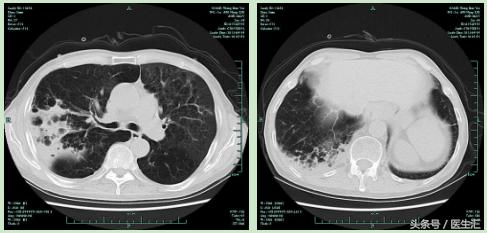

【肺CT】

【提示】该患者有COPD病史,但是本次住院有发热,肺CT上表现为右上肺后段及右下方基底段渗出实变病灶,因此应该考虑为肺炎,由于其在当地医院住院期间发生肺炎,因此诊断医院获得性肺炎

5.7病灶明显吸收复查肺部CT

患者体温正常,咳嗽气急好转,复查肺部CT右上肺及右下肺病灶吸收明显。考虑肺炎治疗有效,给予带口服抗生素出院。

有COPD基础的患者,如果在原有疾病基础上,两肺出现新发的渗出实变病灶,诊断因考虑为肺炎,而不是AECOPD。如在住院期间发生肺炎,应诊断为院内获得性肺炎。该患者CT上病灶主要位于上叶后段及下叶基底段,考虑吸入性的可能性大。治疗上以碳青霉烯类抗生素或酶复合制剂为主